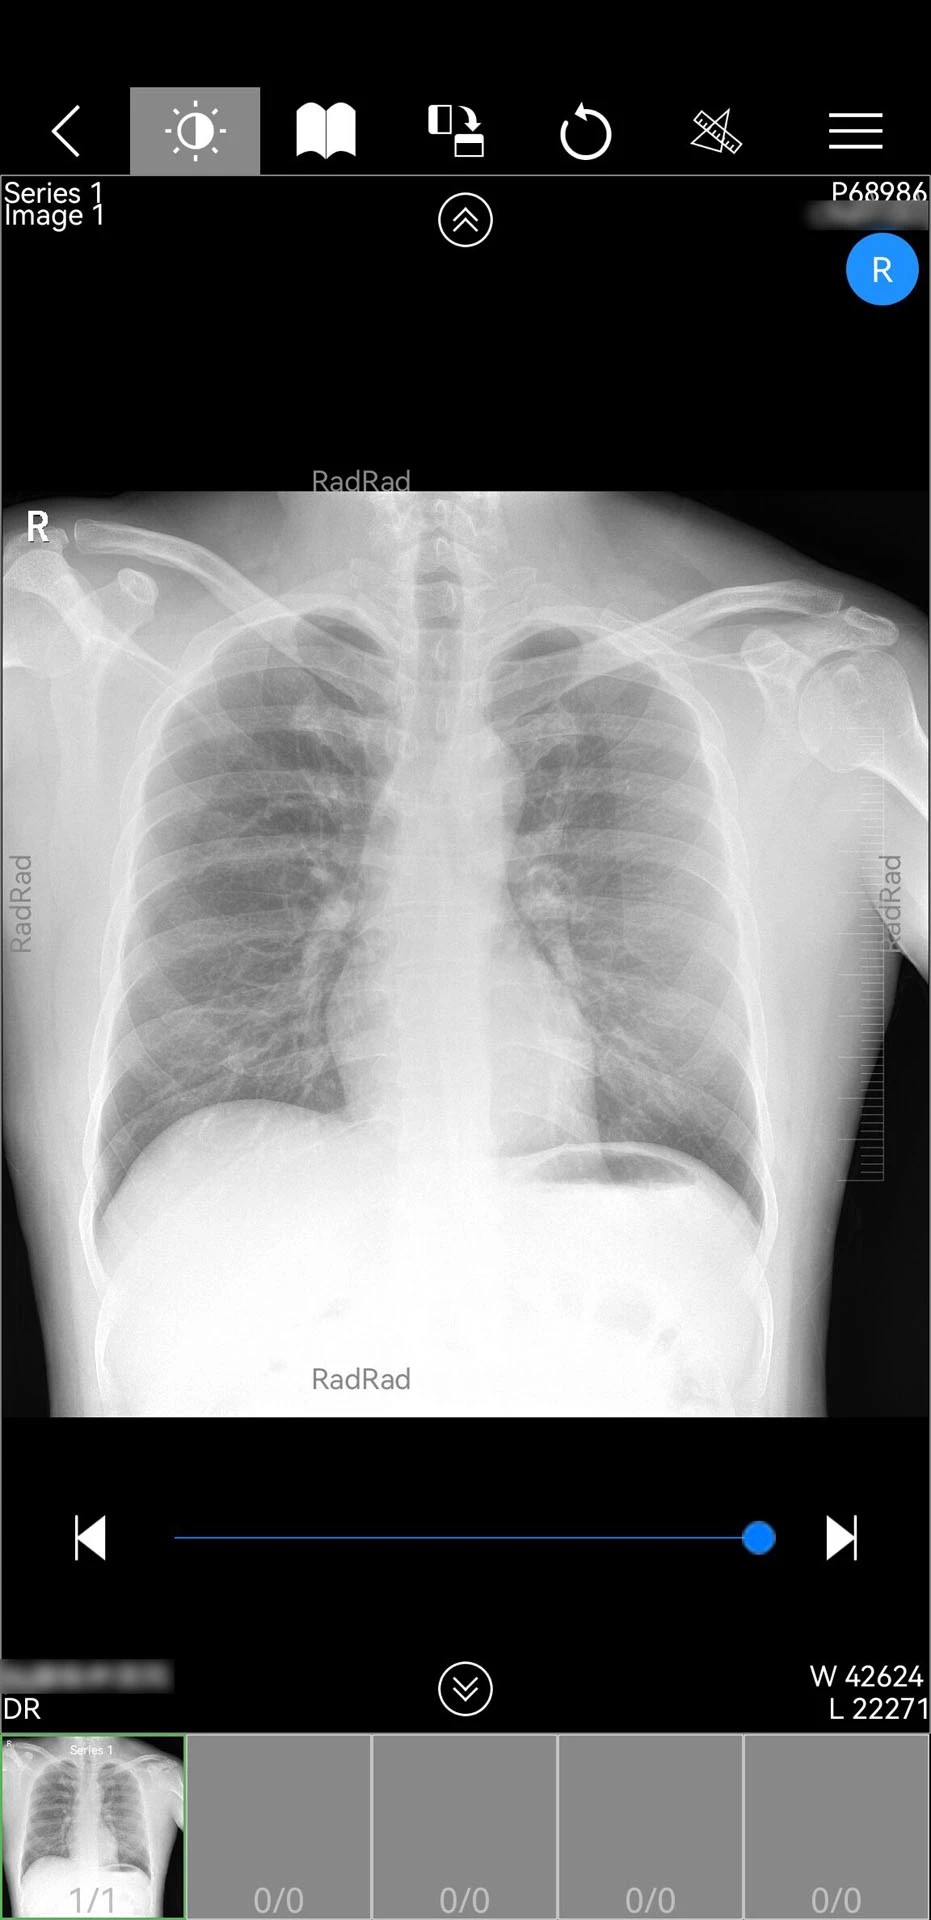

1. 全场景影像支持:支持DICOM格式原始数据解析,可查看CT三维重建、MRI多序列对比等高级影像功能,并通过AI辅助标注病灶位置,提升诊断精度。例如,在肺癌筛查中,系统可自动识别肺结节并计算体积变化率。

3. 智能诊断辅助:内置AI影像分析引擎,可自动生成结构化报告,支持肺结节、骨折等12类常见病的智能诊断。测试数据显示,AI辅助诊断与三甲医院专家诊断结果符合率达92.3%。

1. 核心功能操作:登录后进入“影像中心”,医生可通过搜索患者ID或扫描检查单二维码快速调取影像;在“会诊中心”可发起多人视频会议,共享屏幕标注影像关键点;“患者库”支持按疾病类型、就诊时间等维度筛选病例。

3. 数据互通生态:与医院HIS、PACS系统无缝对接,支持将移动端诊断结论同步至电子病历;同时开放API接口,可接入第三方AI诊断模型,如某三甲医院接入自主研发的肺癌AI模型后,早期肺癌检出率提升18%。